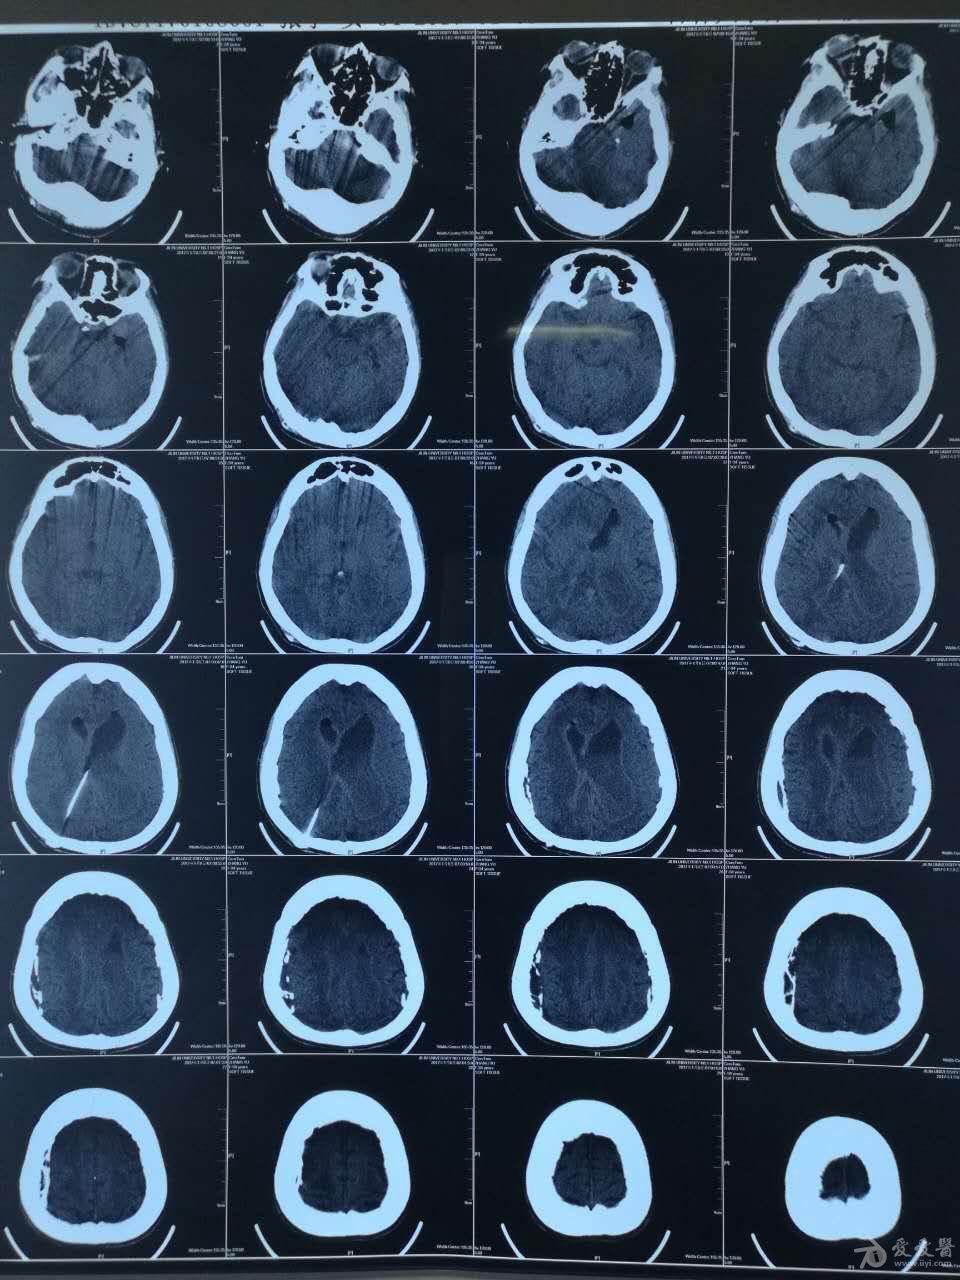

查头ct:后颅窝蛛网膜囊肿,重度脑积水(交通性),双侧小脑蚓部未见,考虑

脑积水ct显示:侧脑室,三脑室扩大有症状的脑积水应该及时手术治疗.

案例59 脑积水